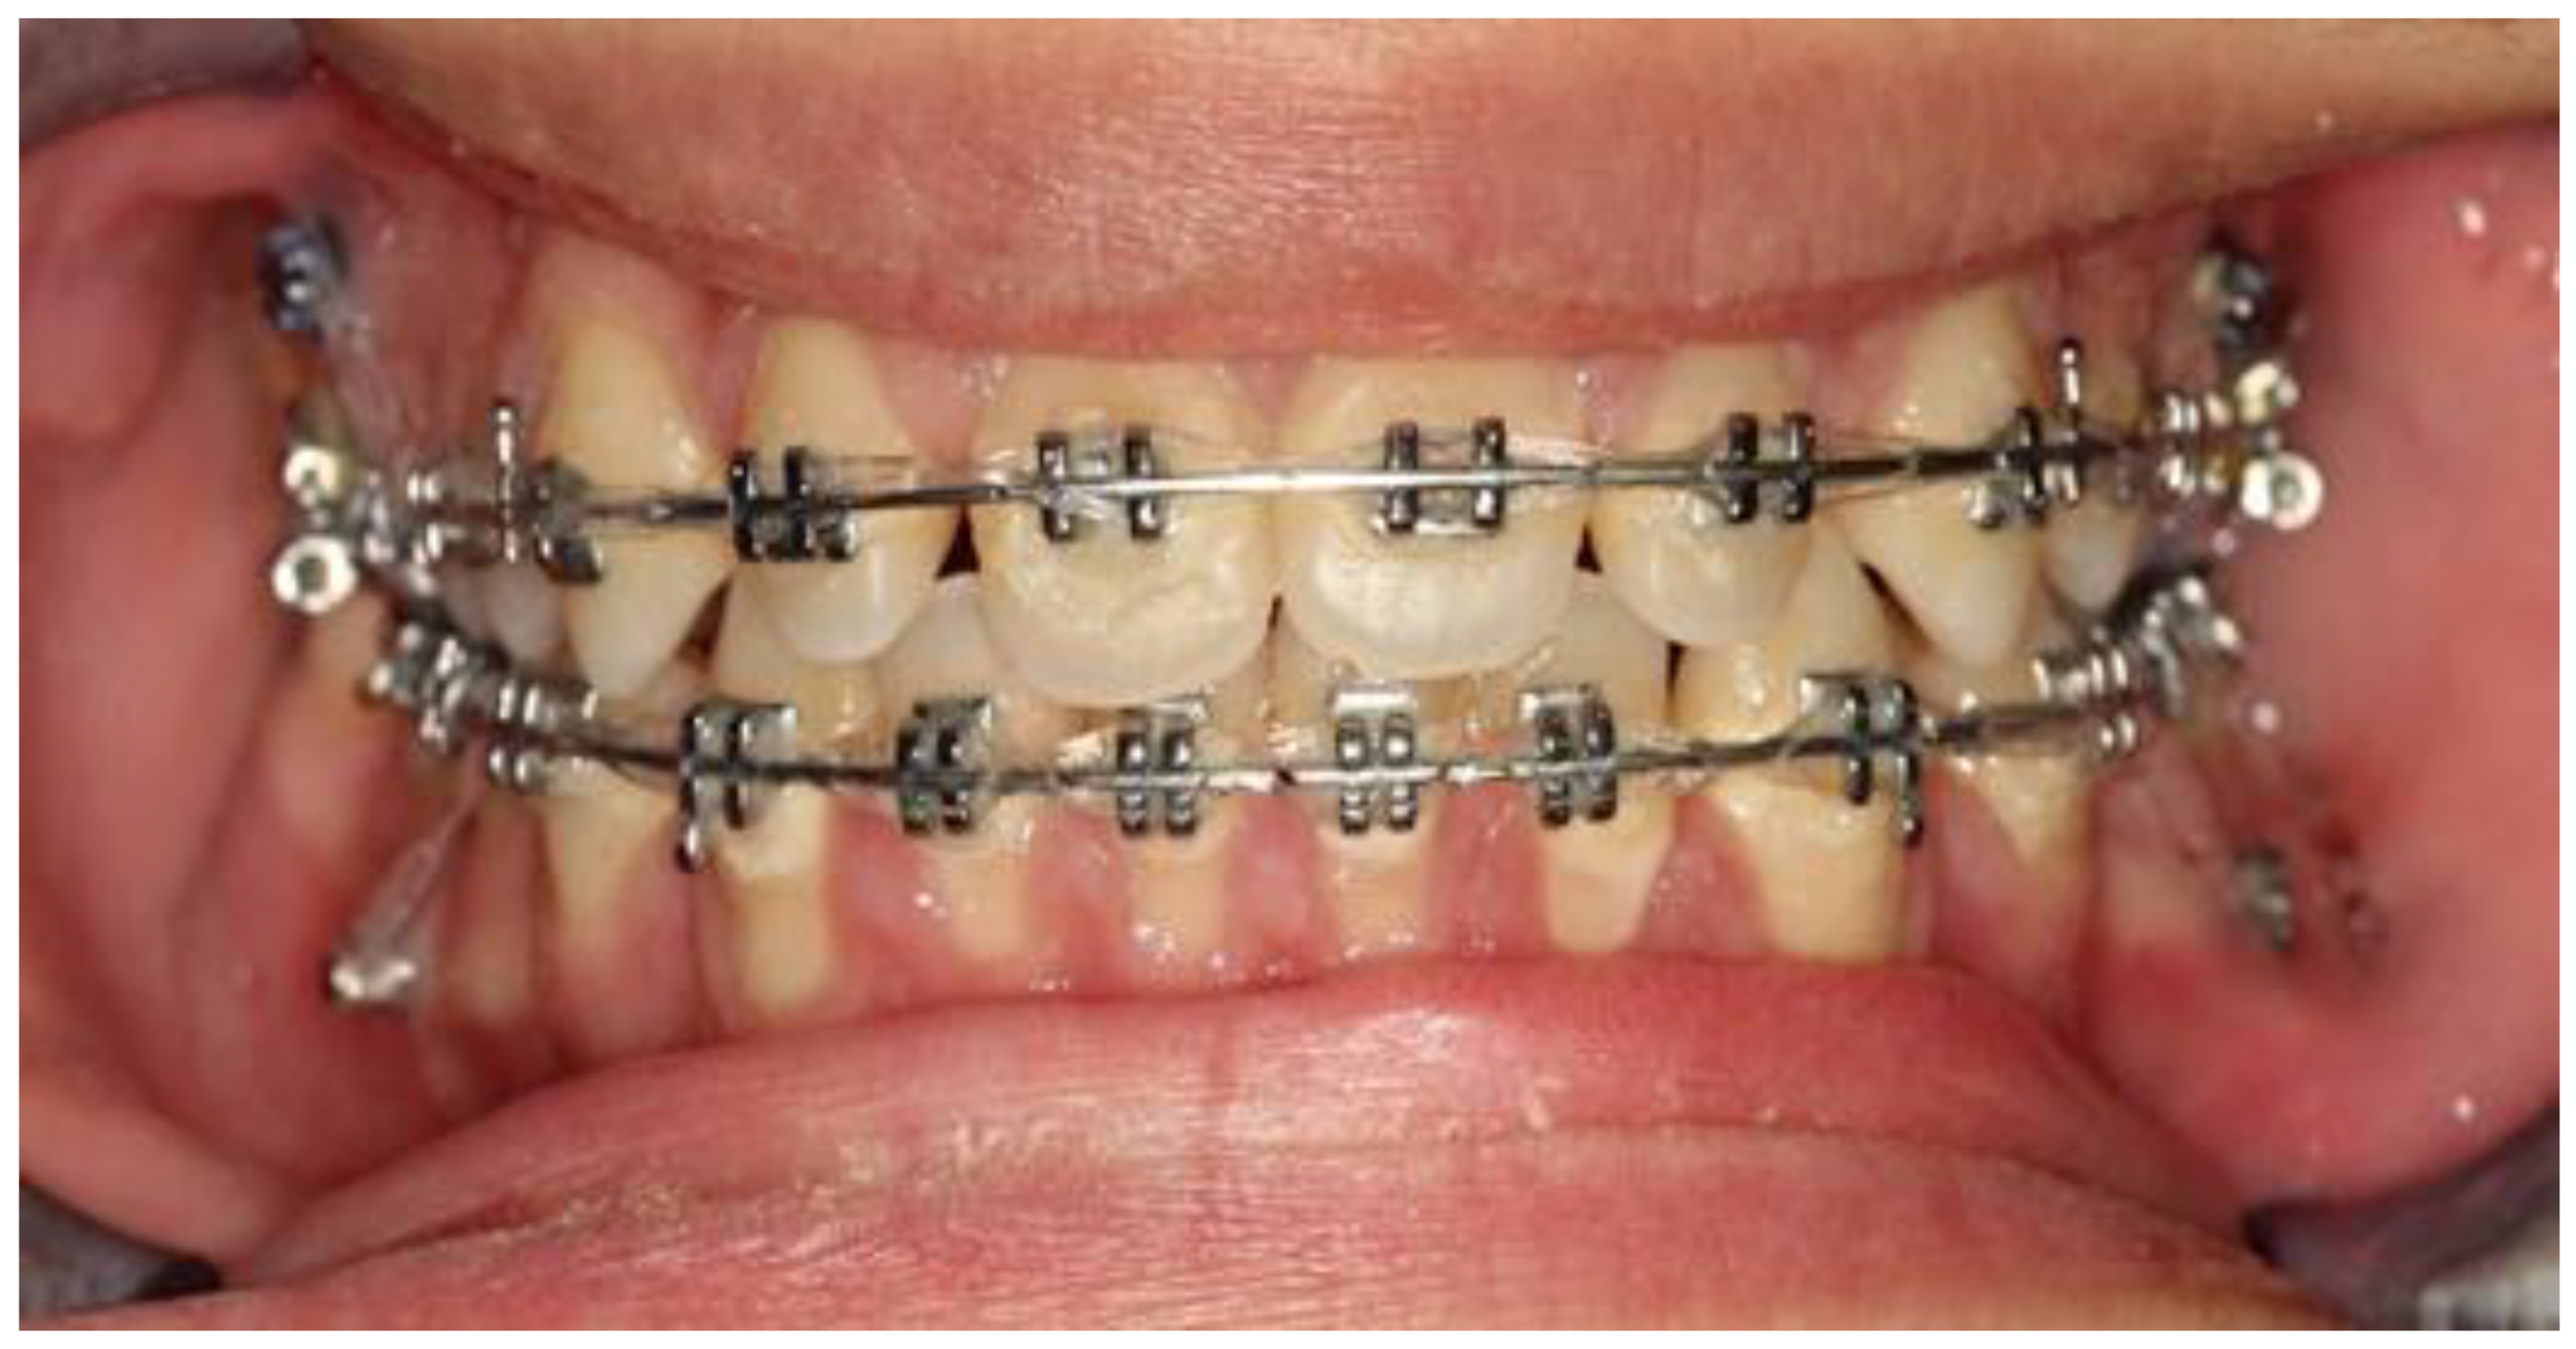

2. Materials and Methods

3. Results